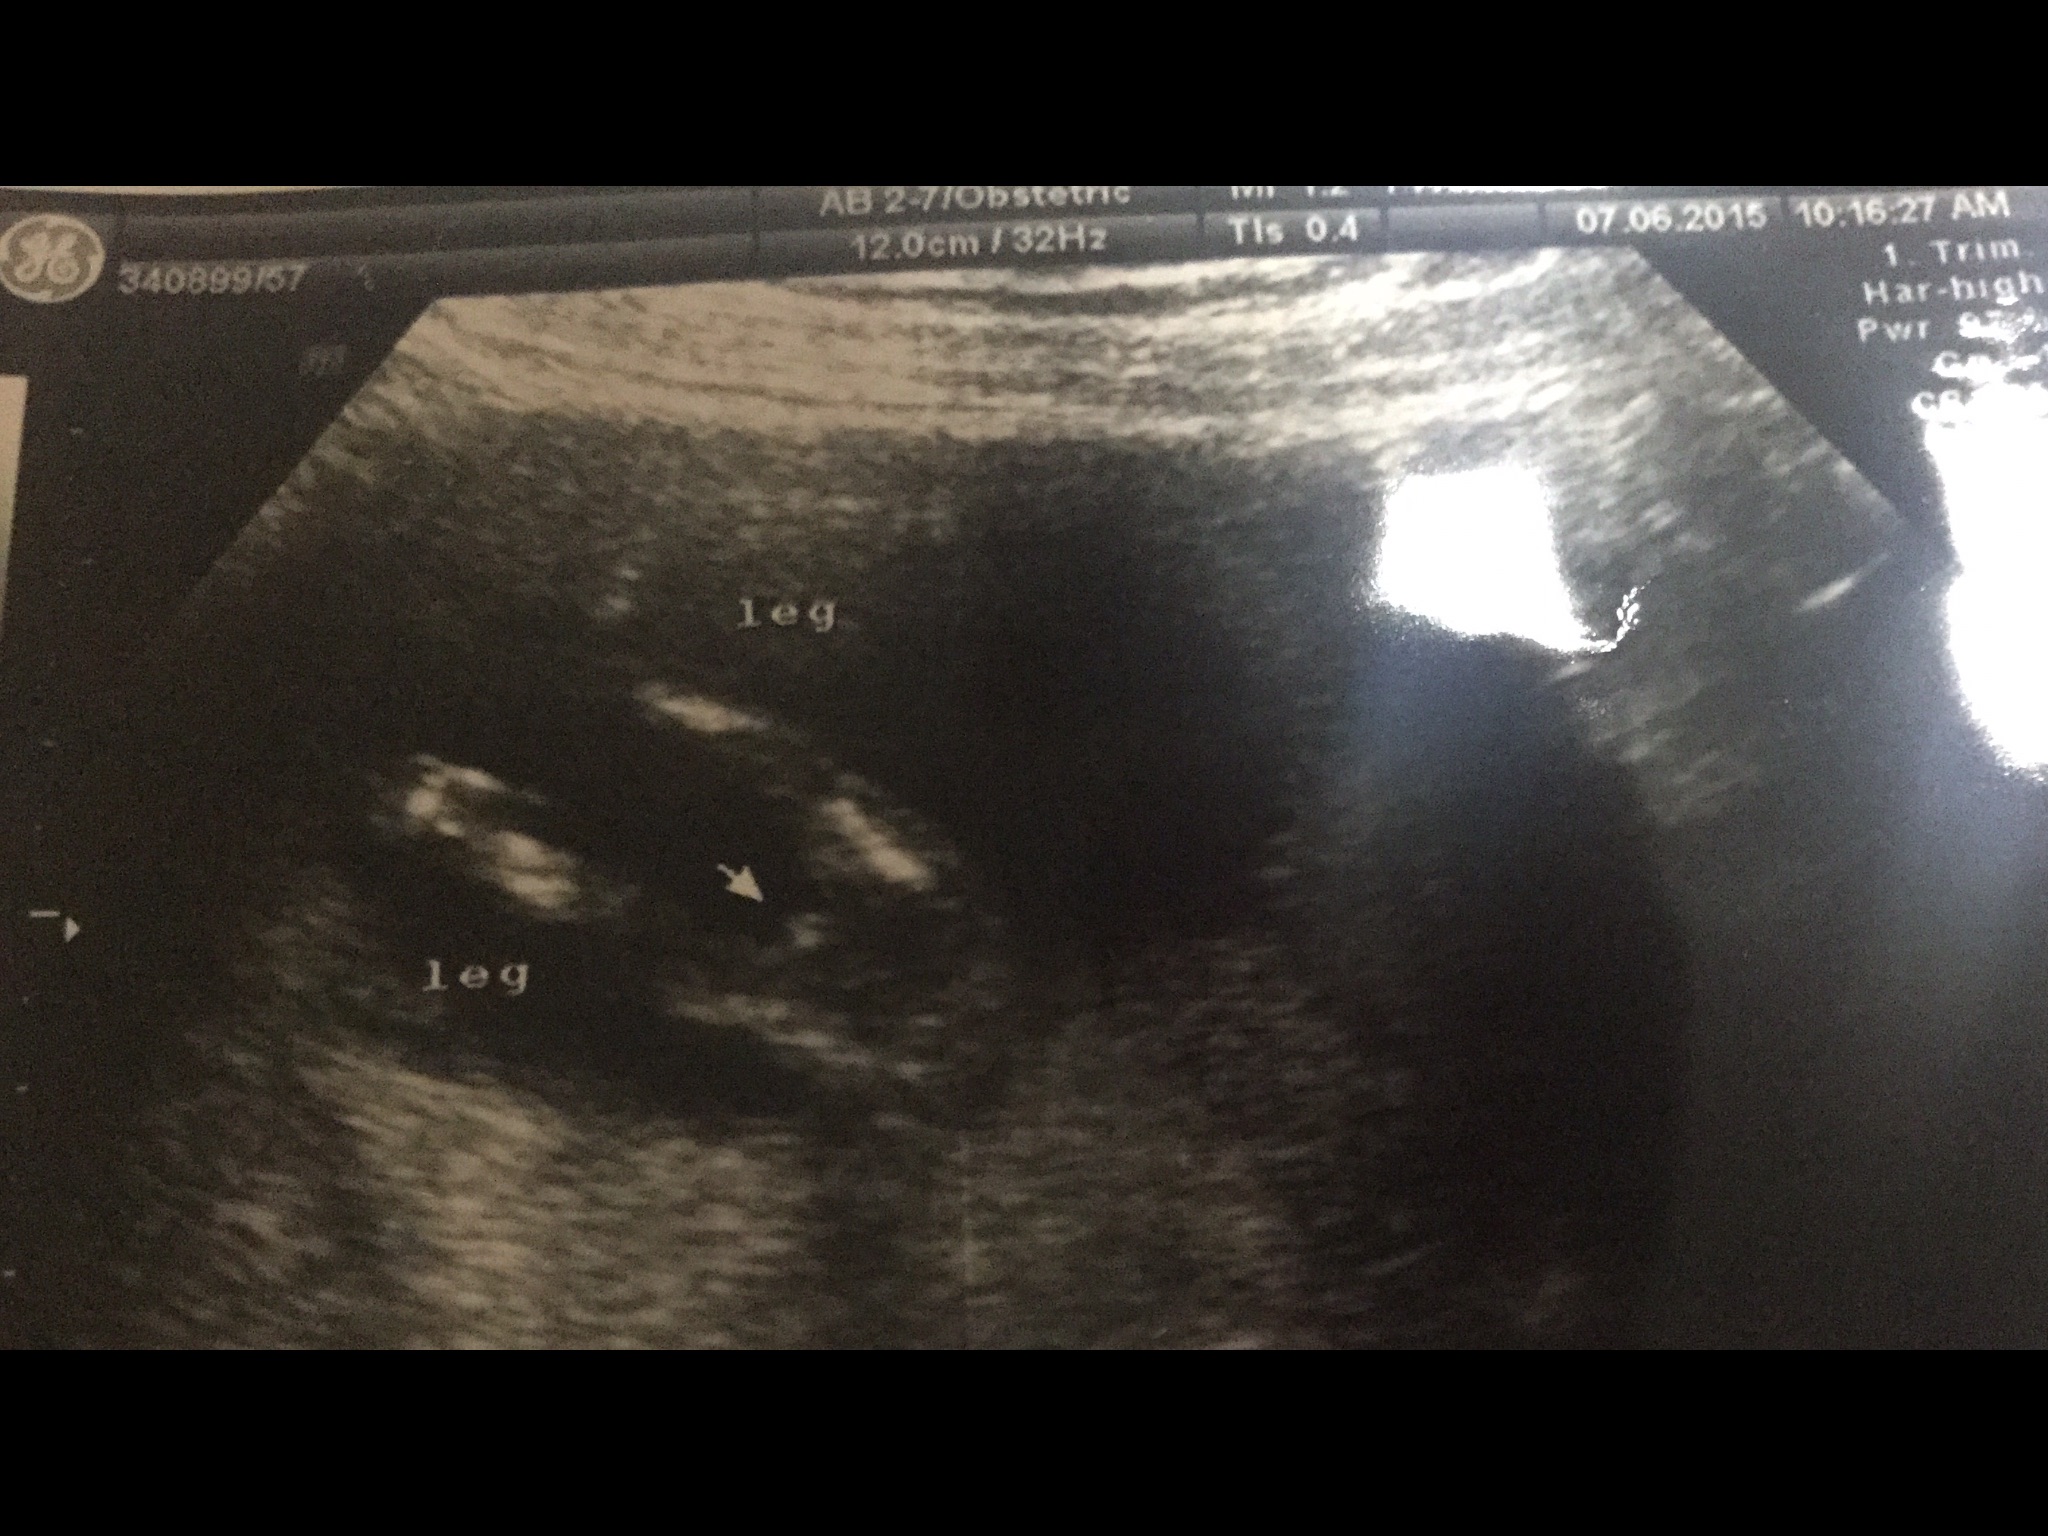

2. ดูจากรูป ขาลูกเราไม่เท่ากันรึปล่าวคะ อันนี้มาดูรูปเองแล้วคิดเอาเองค่ะ